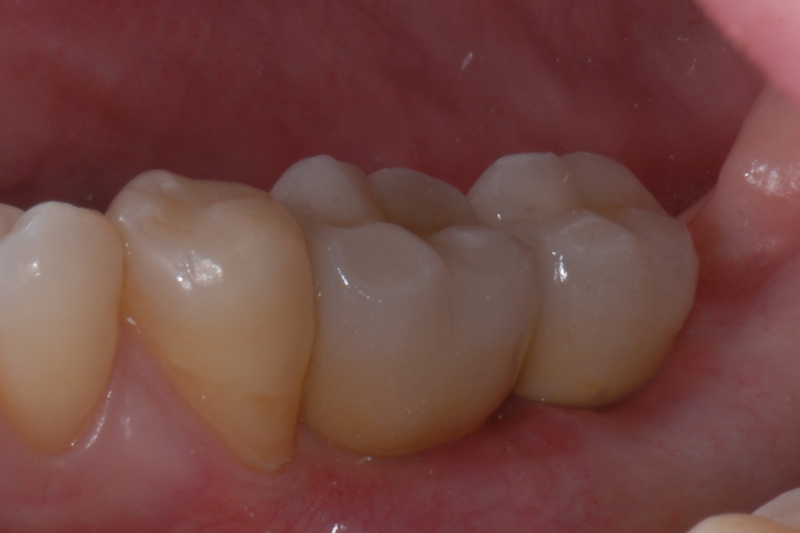

- Status kliniczny po wprowadzeniu odbudowy protetycznej

- status kliniczny po wprowadzeniu odbudowy protetycznej – widok powierzchni okluzyjnej